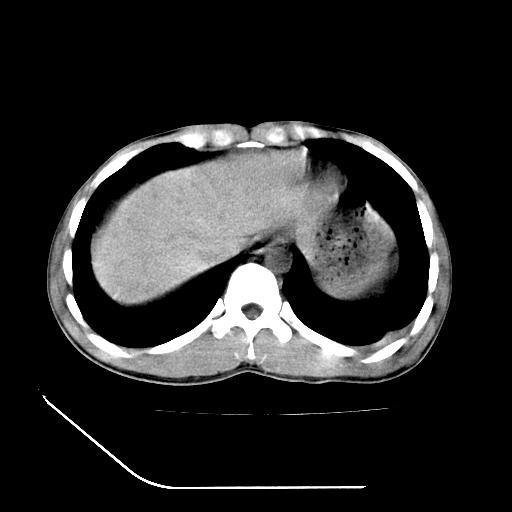

左肾挫裂伤并肾周血肿;

左肾挫裂伤并肾周血肿

支持 : 左肾挫裂伤并肾周血肿

支持:1、左肾挫裂伤并肾周血肿;

2、少量腹水;

3、左肾旋转不良;

4、反射性肠淤张。